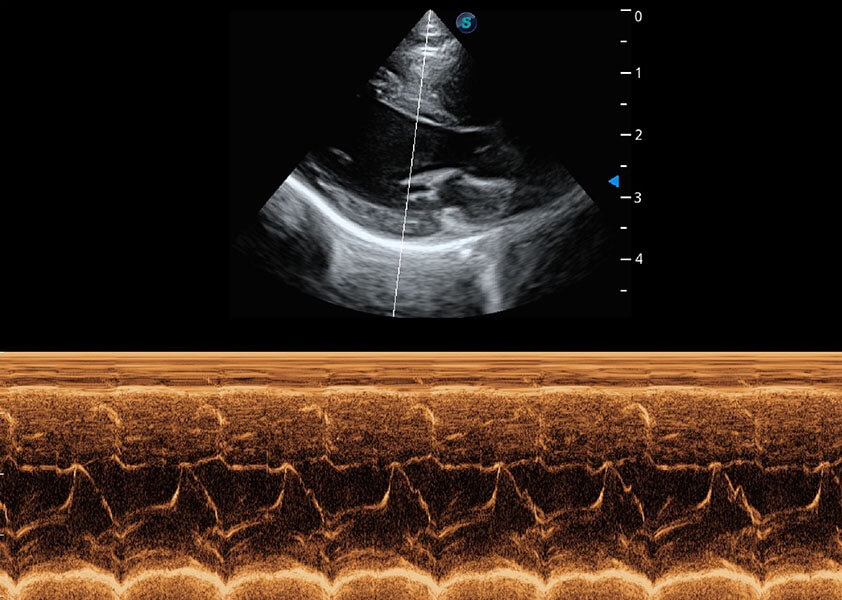

心脏解决方案

ProPet 60 配备了丰富的心脏探头群、先进的成像技术和专业的心脏测量工具,可帮助动物医生为不同体型和生理结构的动物提供心脏和心肌功能的全面评估。

• AMM 解剖M型

通过360度任意调节3条M型取样线,在同一心动周期上观察心脏不同位置的运动曲线,得到准确的心功能测量数据,有效评估心肌运动及左心室功能。

(猫)二尖瓣M型